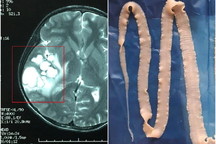

Kết quả thăm khám phát hiện bệnh nhân nhiễm nhiều loại giun sán, đặc biệt là sán dây.

Hình ảnh sán trong cơ của bệnh nhân (Ảnh: Bác sĩ cung cấp).